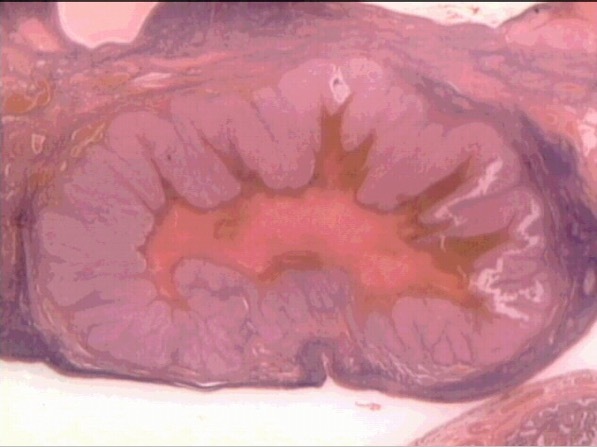

male urethra

female urethra